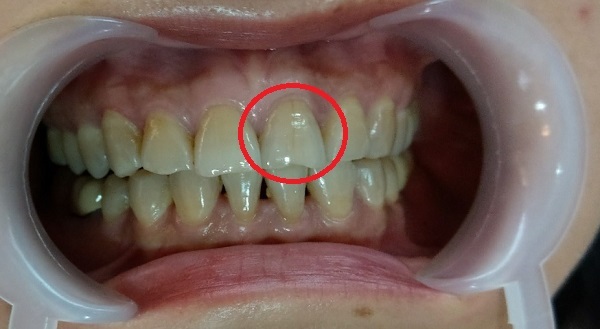

媽咪看到超植這個牙齒美白貼文馬上說她想要做牙齒美白

她說因為工作抽菸加上喝咖啡和濃茶

牙色早就從白變黃很久了....

吳醫師說媽咪植牙的地方顧得很好沒什麼蛀牙

牙齒也算健康乾淨~沒有牙結石

若要做牙齒美白絕對沒問題